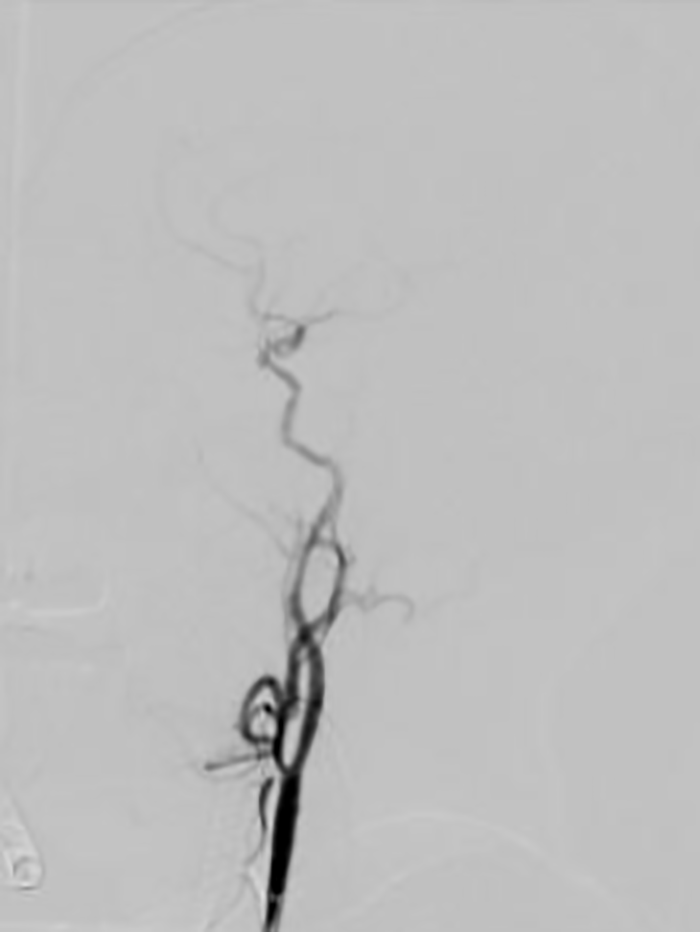

▲患者术后脑血管完全再通

次日患者神志转清,四肢活动自如,家属见状非常激动,对卒中团队迅速高效的“脑卒中绿色生命通道”以及精准的判断和救治能力竖起了大拇指!

▲患者次日神志及肢体肌力逐渐恢复